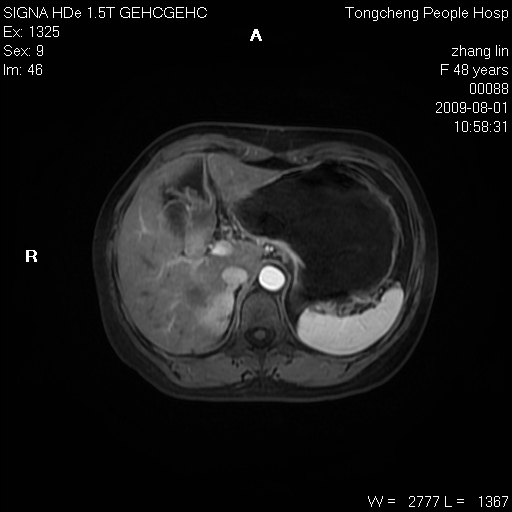

女,48岁。健康体检,彩超发现右肾占位性病变。平素健康。

临床诊断:右肾占位性病变,性质待定(囊肿?肿瘤?)。

上中腹部mr平扫+增强扫描,图像如下:

右肾上极见一类圆形病灶,t1wi呈等信号t2wi呈等高混杂信号,三期增强无强化,边界清---考虑囊肿出血。

同反相位均表现为等信号,病变无强化,考虑含蛋白的囊肿可能,弥散加权相或许有些帮助,

慢性胆囊炎